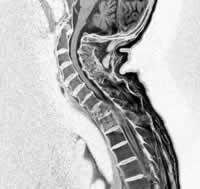

二.MIR檢查

對椎間盤突出、軟組織損傷及脊髓受累程度的判定意義較大,有條件者應爭取之。